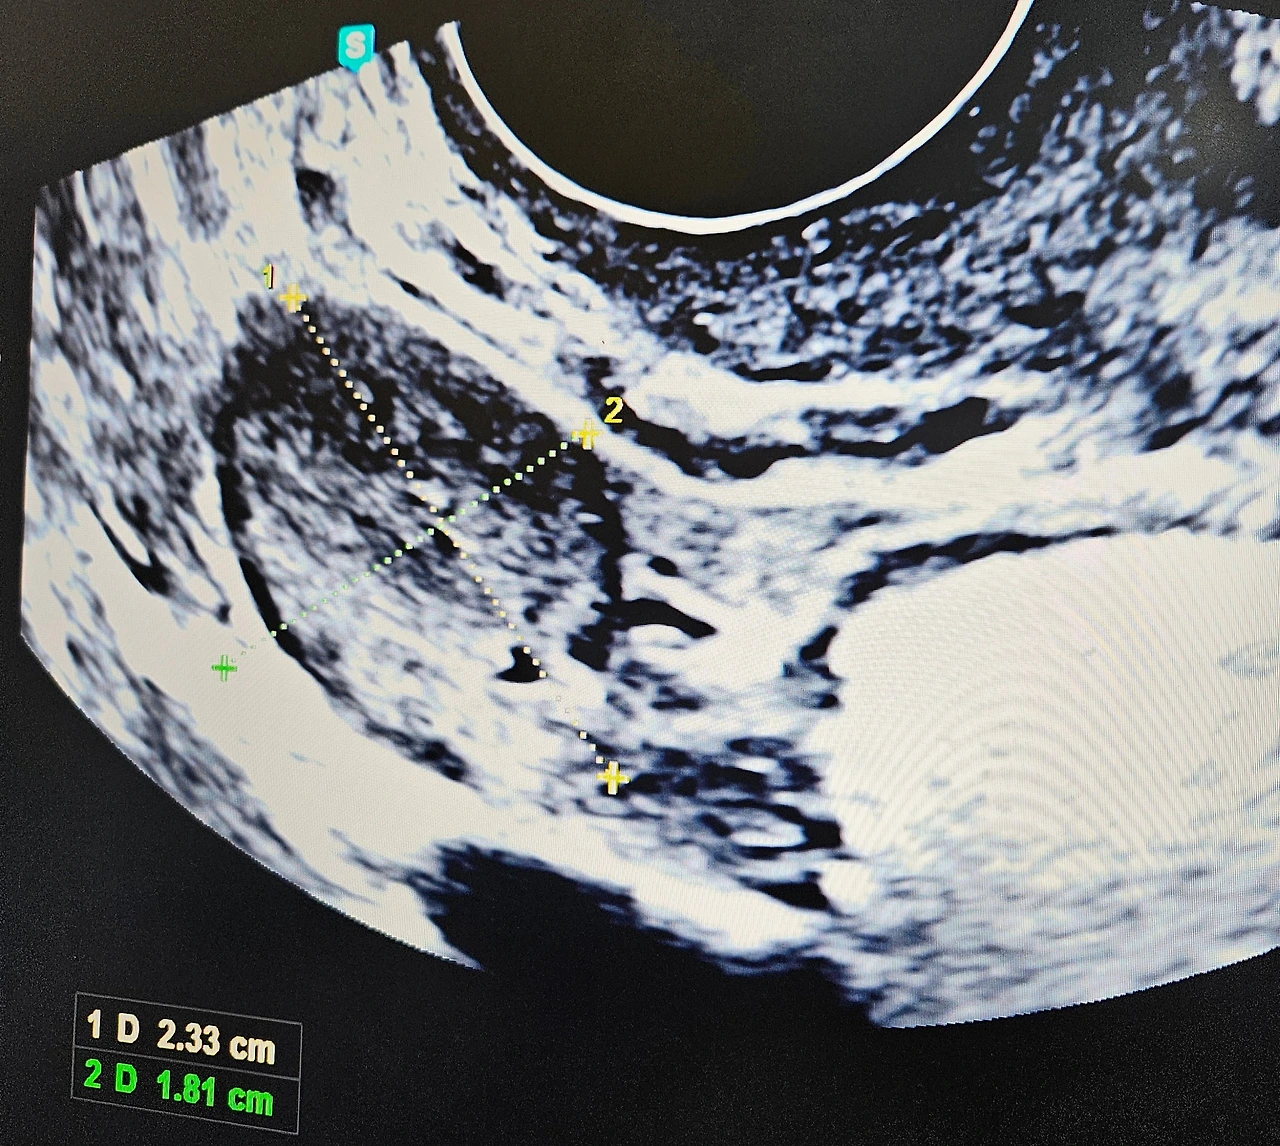

배란초음파로 본 난포크기는 1.6mm였고, 처음으로 의사에게 3일의 '숙제날'을 받았다.

(*난포는 하루에 0.2mm 정도 자라고, 2.0mm 이상으로 자라면 터져서 난자가 방출된다)

숙제 후에는 난포가 잘 터졌는지 확인해야 해서 26일, 다시 내원했다.

초음파를 보던 의사 선생님이 말하길,

"어? 난포가 안 터졌네?"

29일, 3차 배란초음파 보는 날.

"잘 터졌네요. 축하해요."

임신한 것도 아니고, 난포가 잘 터진 것도 축하할 일인 줄 이 날 알았다.